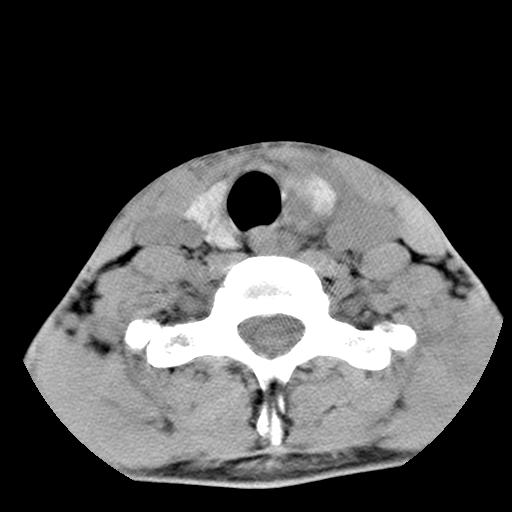

标题: CT15118:f-27y,左颈部肿一个月,无发热、无压痛 [打印本页]

标题: CT15118:f-27y,左颈部肿一个月,无发热、无压痛

1、甲状腺左叶病变:腺瘤?结节性增生?其他?

2、上极周围间隙病变。

3、2者关系?

左侧甲状腺肿大,密度不均.同侧甲状软骨似有破坏(建议传骨窗).左侧颈静脉增粗,各组织之间分界不清,有多个肿大淋巴结.甲状腺肿并感染?临床症状不符.淋巴结核?请结合其他检查.